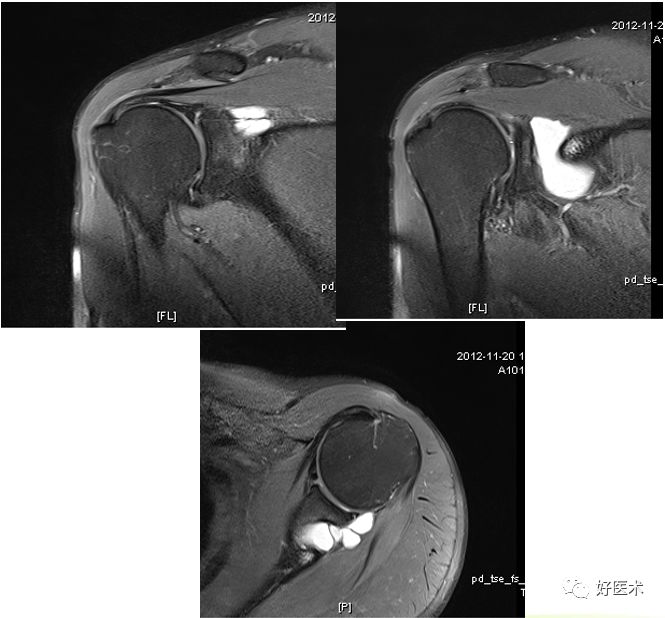

骨性Bankart病变

MR间接关节造影1.5T轴位T1W脂肪抑制(TR=460s,TE=90s)